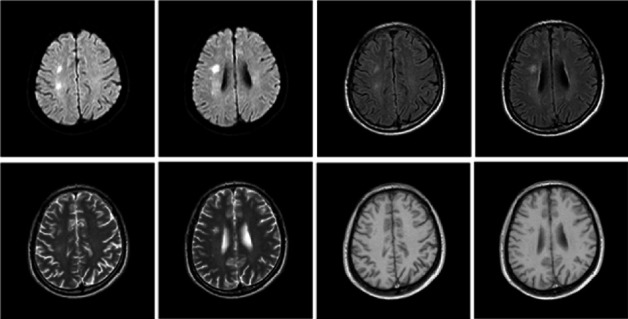

In order to discuss the clinical and MRI features, diagnosis, and prevention of myelin oligodendrocyte glycoprotein antibody-associated disease (MOGAD), we reported an adult case of MOG antibody-related disease misdiagnosed as cerebral infarction. This patient's first clinical symptom was limb weakness, that different from previous reports of MOG antibody-related diseases, such as brainstem encephalitis, neuromyelitis optical, and transverse myelitis. The main treatment plan is high-dose corticosteroid therapy combined with immunoglobulin therapy. This case indicated that some MOGAD patients lack of specificity in the clinical manifestations and imaging perhaps would be misdiagnosed as cerebral infarction, encephalitis, immune peripheral neuropathy, MS, NMOSD, and other diseases. For patients with atypical clinical manifestations or imaging, it is especially important to take antibody detection as early as possible to make correct diagnosis and active treatment in time to avoid disability.

Abstract Image